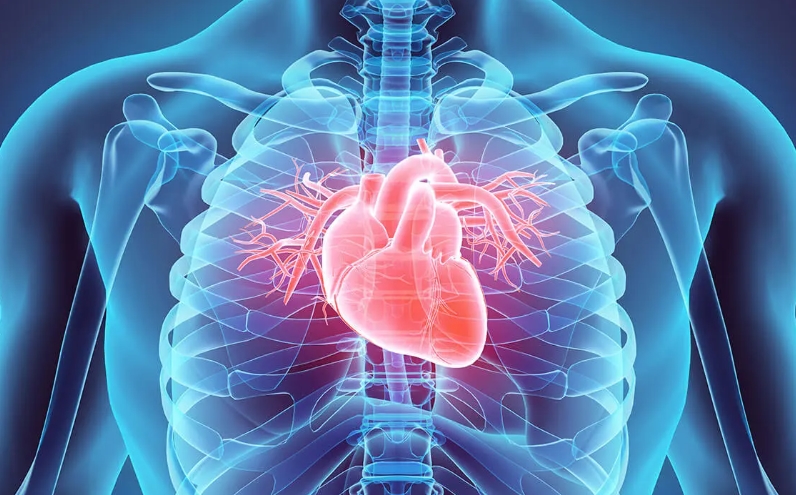

SİNİR SİSTEMİ VE KALP SAĞLIĞINI ETKİLİYOR

Khodakovsky, bu maddelerin sinir ve kardiyovasküler sistemlerde kronik problemlere bile yol açabildiğini dile getirdi.

Metanolün özellikle tehlikeli olduğunu ve körlük dahil görme sorunlarına yol açabileceğini vurguladı.

Doktor, metanolün 2000 yılından bu yana yasaklandığını ancak halen temizleyicilerde ve antifrizde kullanıldığını hatırlattı.

Ayrıca birçok deterjan vücutta biriktiğinde kısırlığa neden olabilen aktif maddeler içeriyor.